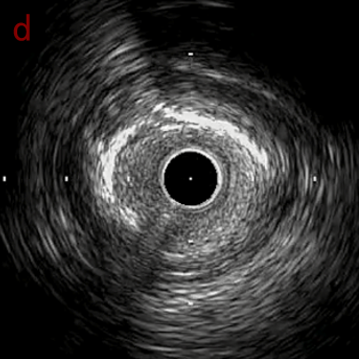

IVUS after POBA

IVUS imaging after POBA

OASによる石灰化部位は良好なsandingができており、POBAを行うことで石灰化にcracksを認めたため予定通りDCBに。

手前のlipid plaqueを含む病変はステント留置。

DCB 2,5*20mm/ Stent 3.0*24mm

責任病変にはDCB、手前のlipidな部位にはステントを留置